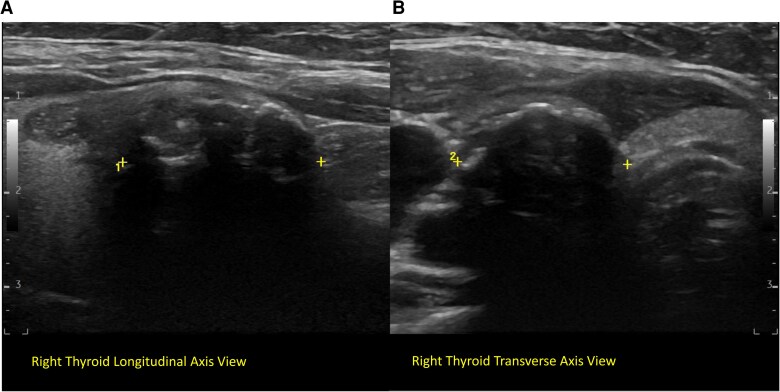

The frequency and impact of multiple driver mutations have not been extensively explored in papillary thyroid carcinoma (PTC), in which driver mutations are most commonly solitary. We present a case of a 62-year-old female who was found to have a 2.6-cm classical, nonaggressive-appearing PTC. A next-generation sequencing panel assessed the tumor for mutations. Five unique single nucleotide sequence variants, none of which was seen in The Cancer Genome Atlas study on PTC, were found: BRAF D594N, NRAS Q61H, PIK3CA G1007R, PTEN R335*, and PTEN Y225*. We believe that 5 pathogenic variants are the highest reported number for a primary PTC resection specimen to date. The observed typical PTC behavior may be due to a weaker strength of the individual pathogenic variants to drive oncogenic processes. In this case, the high number of genetic alterations did not translate into aggressive histopathology or clinical course.